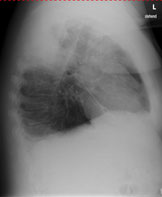

Einer Ihrer Patienten wird wegen einer Pneumonie seit 10 Tagen antibiotisch behandelt. Sie veranlassen eine Thoraxröntgen zur Verlaufskontrolle.

Hier sehen Sie das Kontrollröntgen:

Thorax seitlich